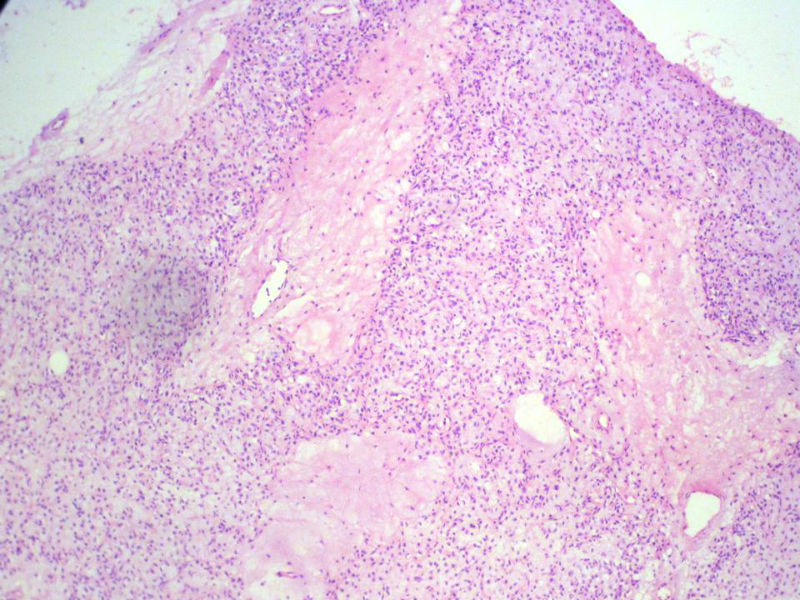

男,27岁,右股骨上段皮下肿物1年余,无明显疼痛,检查肿物明显隆起于皮下,边界清楚,手术完整切除肿物。肉眼,肿物6X6X5厘米,外观多结节状,似有包膜,切面灰白色,质韧。

特别提示:镜下核分裂3-4/HP.

3. 本例组织学改变与粘液性脂肪肉瘤,粘液样纤维肉瘤,纤维粘液样肉瘤,骨外粘液样软骨肉瘤都有重叠之处,且镜下并未见典型结构。由此,免疫组化结果就尤显重要。特别是专业书籍提到,突触素或嗜铬素阳性,对鉴别诊断有重要意义。我用CGA,也是在以上几个肿瘤中举棋不定而为。NSE和CK没用,其实我想用更多的抗体来证实更多的东西,但患者的经济条件不太好,遗憾!